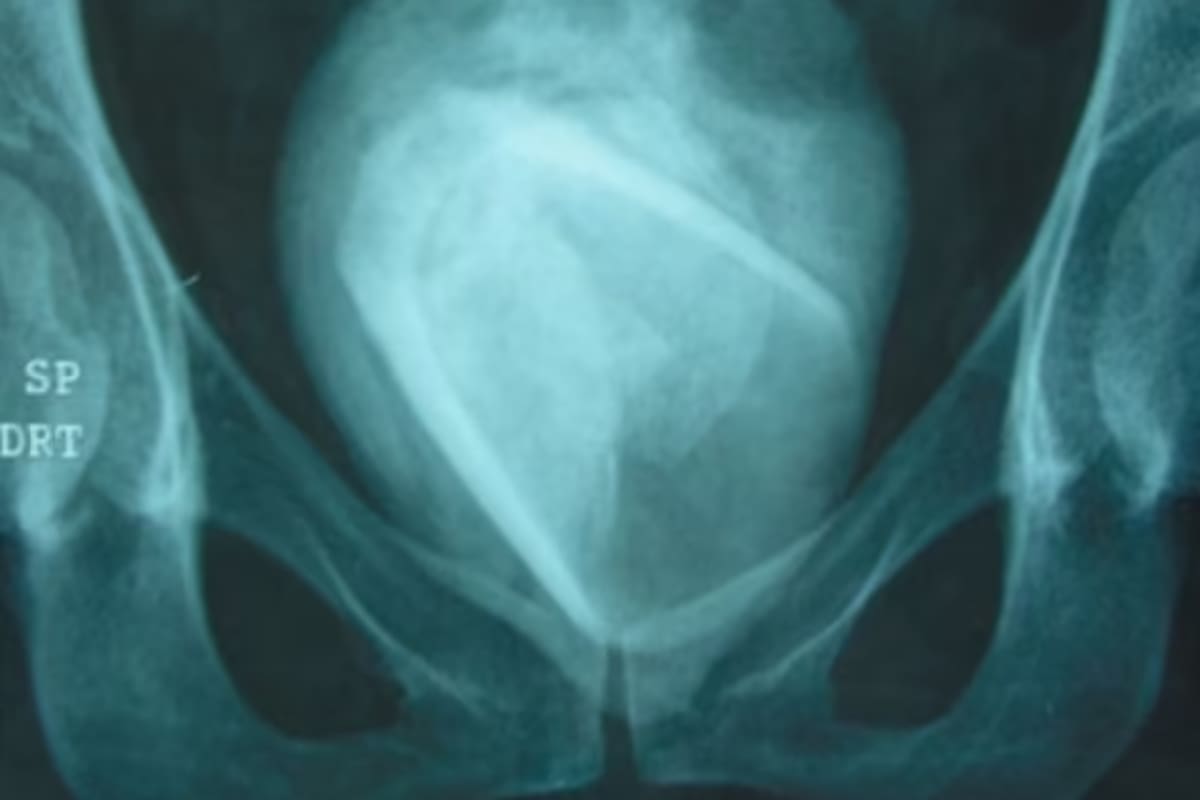

Al hacerle estudios, los médicos descubrieron que se había formado un cálculo de ocho centímetros de ancho. Asombrados por este hallazgo, luego de la intervención pertinente descubrieron que en su interior había un vaso. Según contó la paciente, se había introducido el objeto hace cuatro años y la piedra estuvo allí durante todo ese tiempo, según fue publicado en Urology Case Reports.

El enorme tamaño del cálculo no pasó para nada desapercibido, sobre todo si se tiene en cuenta que usualmente no son visibles para el ojo humano sin el uso de algún artefacto. Según reveló la paciente, se había introducido el vaso en la uretra hace cuatro años como parte de un juego sexual. Increíblemente, quedó alojado allí y nunca fue a que se lo extrajeran en todo ese tiempo.

Para retirarlo del cuerpo, se realizó una cistolitotomía y se pudo quitar el cálculo exitosamente. Luego de dos días de recuperación posoperatoria, la mujer fue dada de alta y volvió a su hogar sin inconvenientes.